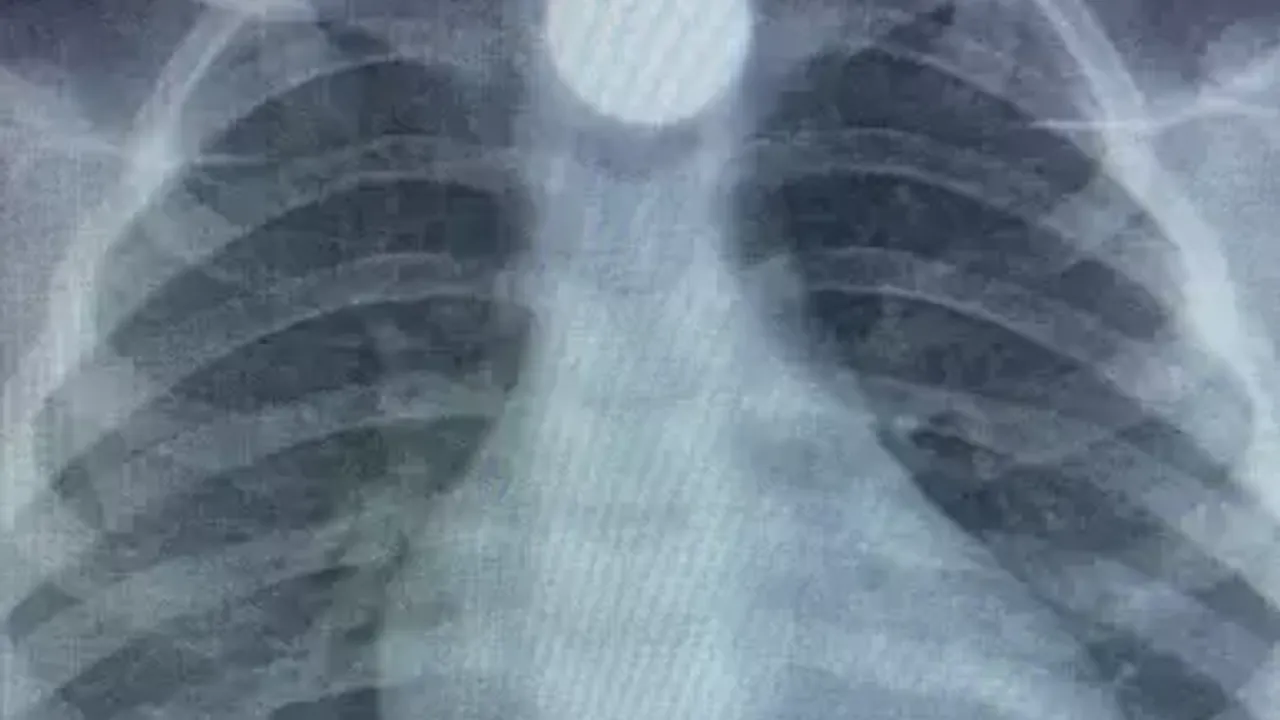

Hastanede yapılan ilk muayene ve röntgen çekimlerinde, 50 kuruşluk madeni paranın B.K.’nin yemek borusunda takılı kaldığı tespit edildi. Sağlık ekipleri, küçük çocuğa acil müdahalede bulunarak durumu stabilize etti. Ardından B.K.’nin daha kapsamlı bir tedavi alması için ambulansla Bursa Yüksek İhtisas Eğitim ve Araştırma Hastanesi’ne sevk edildi. Burada gerekli tetkiklerin yapılmasının ardından paranın çıkarılması için gerekli işlemler planlandı.